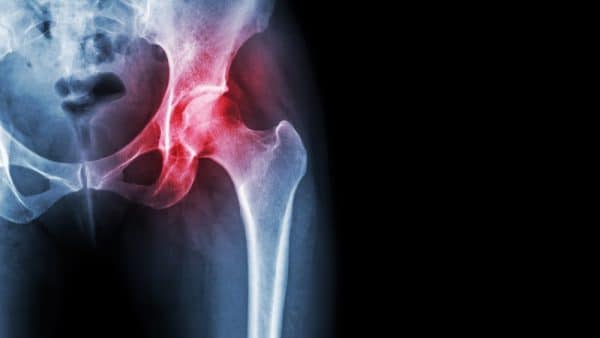

Hip Osteoarthritis

Hip OA is one of the top contributors of global disability. It is prevalent in 10% of people above 65, and 50% of these cases are symptomatic. The most common symptom of hip OA is pain around the hip joint, which develops slowly and worsens over time.

arthritis of the hip joint